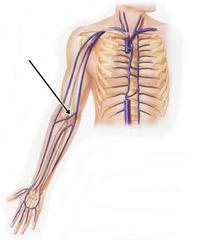

Basilic Vein

Cephalic vein

Median cubital vein